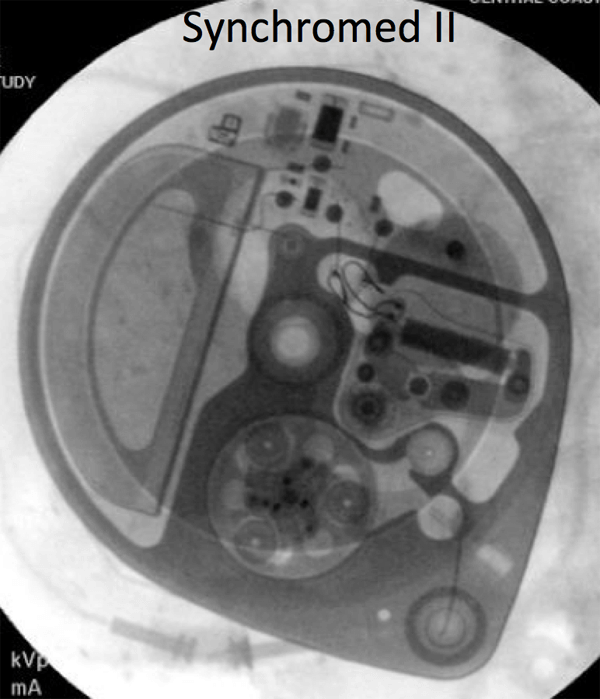

- A policy is being developed with the Pain Management Service to expedite the scanning of patients with Medtronic Synchromed II pumps, which are MRI conditional at 1.5T. The identity of the pump must be documented before the MRI scan, and then confirmed at the time of the scan.The pump program needs to be check after the MRI: for outpatients, this can be done at a pre-scheduled appointment with the managing service; inpatients will need to have the Pain Management team perform this check.

If there is any doubt about the suitability of a device for MRI, or about management of a device before and after MRI, contact the Neuromodulation Service (lawrence.poree@ucsf.edu). Below are x-ray images of the common Synchromed II pump and the two pumps that should not be imaged without outside consultation and management: Prometra I and II pumps.